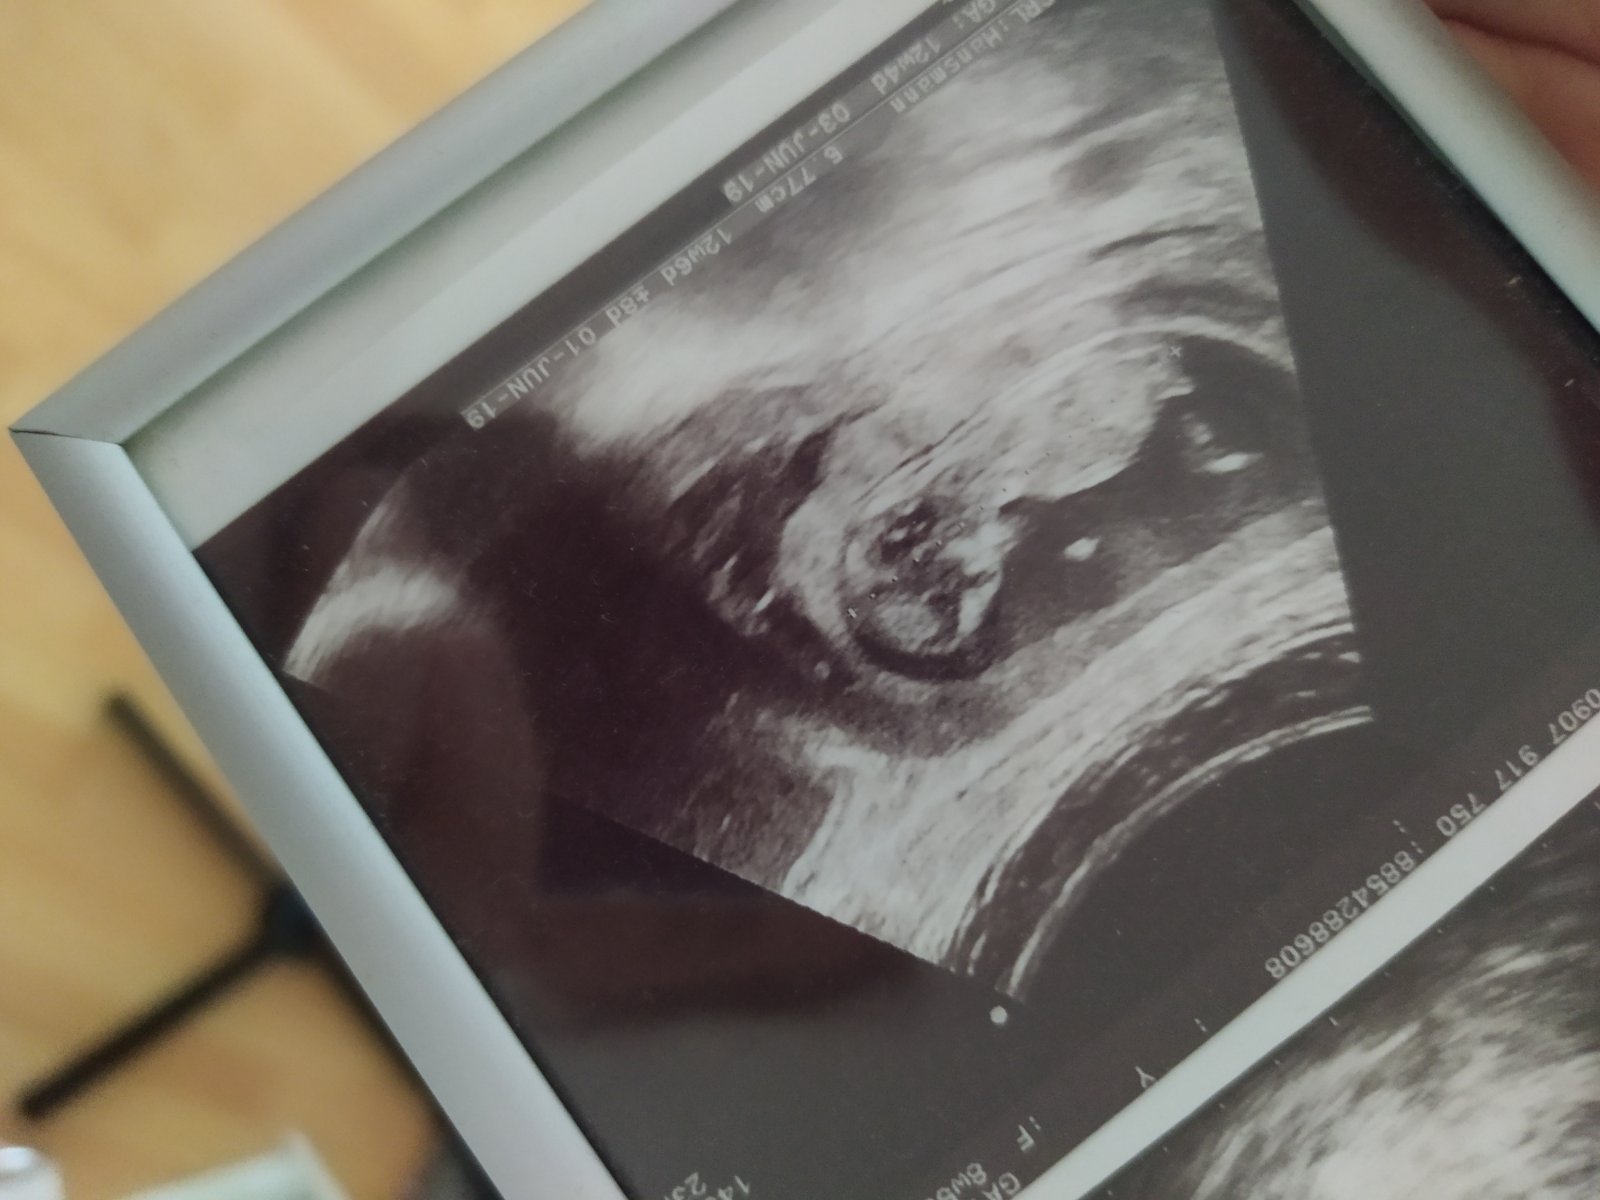

Na fotke je len časť toho hematomu, tú druhú, kde bol cely si nechal doktor.